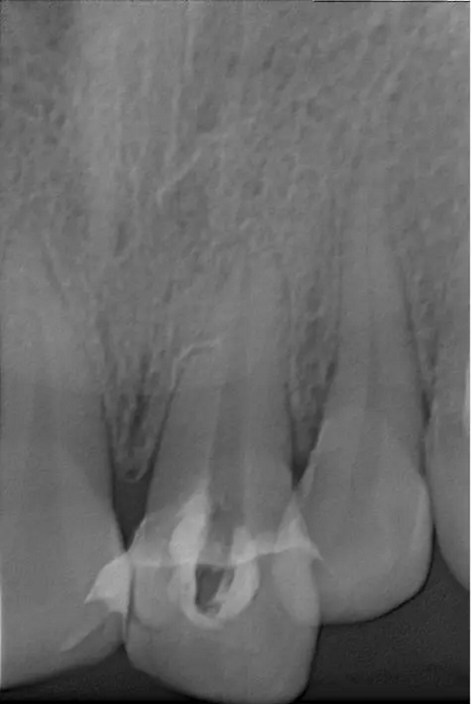

翻瓣去除側(cè)穿超出的牙膠尖

側(cè)穿超出的牙膠尖